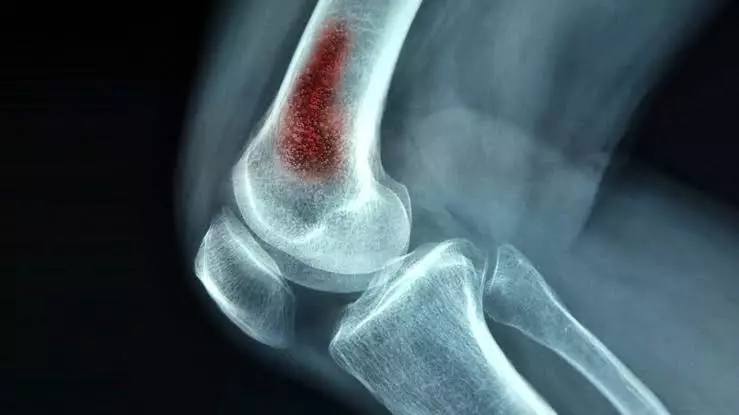

التهابات العظام والمفاصل من المشكلات الصحية الشائعة التي تؤثر بشكل مباشر على الحركة وجودة الحياة، خاصة مع التقدم في العمر أو اتباع نمط حياة غير صحي.

وتعد ممارسة الرياضة بانتظام تساعد على تقوية العضلات المحيطة بالمفاصل، ما يقلل الضغط الواقع عليها ويحميها من الالتهابات والتآكل. وينصح المتخصصون بممارسة أنشطة خفيفة إلى متوسطة مثل المشي، السباحة، وتمارين الإطالة، خاصة للأشخاص الذين يعانون من آلام الركبة أو الظهر.

وتقوية العضلات لا تهدف فقط لتحسين المظهر، بل تلعب دورًا أساسيًا في دعم المفاصل وحمايتها من الإجهاد. فكلما كانت العضلات أقوى، قلّ الحمل على المفاصل، ما يقلل فرص الإصابة بالالتهابات المزمنة.

أيضا زيادة الوزن تمثل عبئًا إضافيًا على المفاصل، خاصة مفاصل الركبتين والعمود الفقري، ما يسرع من تآكلها. لذلك يُعد الحفاظ على وزن صحي من أهم العوامل التي تقلل خطر الإصابة بالتهابات العظام والمفاصل وتخفف من حدّة الألم لدى المصابين.